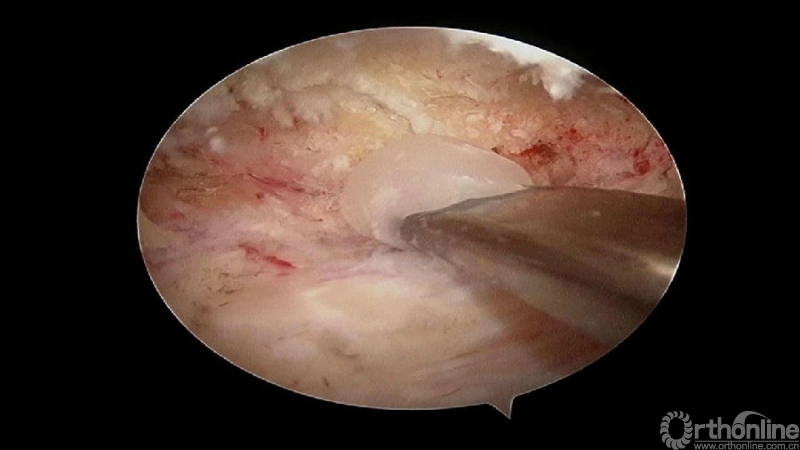

颈椎内镜下单侧入路双侧减压(ULBD)中,减压的难点还是在于识别棘突与椎板的移行部位及对侧结构的显露。

临床上,0°镜子绝对是颈椎UBE的最好用的镜子,但是30°的镜子对侧中线结构的显露及对侧结构的显露具有更广角的视野。在进行同侧减压之前,中线结构的显露是关键。

手术步骤:

1.骨赘位于左侧,选择右侧入路做C4/5椎板切除减压;

2.显露骨赘的内侧面及上下缘;

3.从游离骨块的背侧开始,用磨钻将骨块打薄,然后将骨块的底面与脊髓表面仔细分离,将游离骨块摘除;

4.进一步加深移除骨赘的残余部分,直到显露出对侧的神经根及关节突关节的内壁;

术中操作要点

1. 术中如何确定中线?

2. 术中骨赘的界限?

3. 如何确定对侧结构?

4. 如何确定减压范围?

5. 减压完成后的止血非常重要,高效的止血方法有哪些?